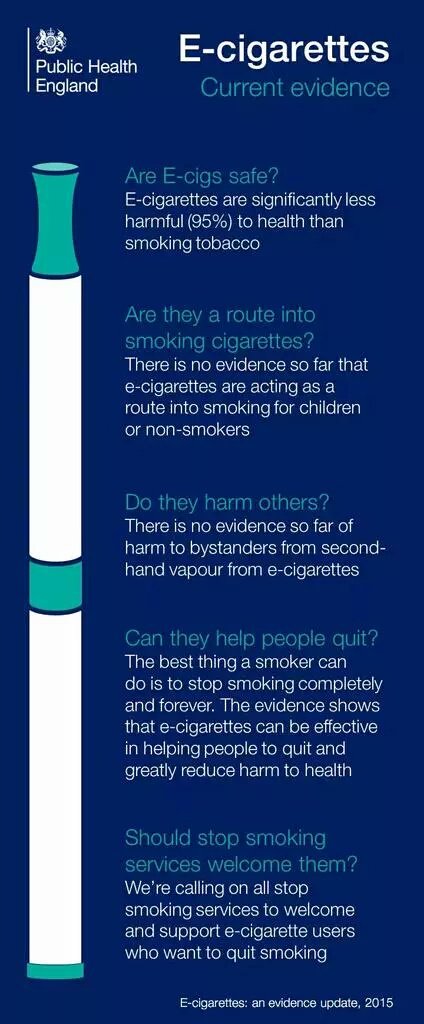

.U.S. Surgeon General Absolutely. Time to embrace the most effective & popular way on the planet #VapingTruth